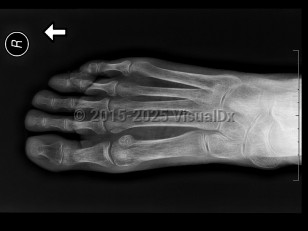

Osteoporosis is a metabolic bone disease characterized by progressively declining bone density with decreasing bone strength and structure, resulting in increased fracture risk, especially vertebral and hip fractures. Fracture is the only clinical manifestation. The condition begins when osteoclast function (bone resorption) occurs more than osteoblast function (bone formation). This results in increased and irreversible bone porosity in the cortical and cancellous (trabeculae) osseous tissue. Risk factors include advancing age, female sex, and postmenopausal status. Corticosteroid use, especially long-term use, can be an important predisposing factor for osteoporosis.